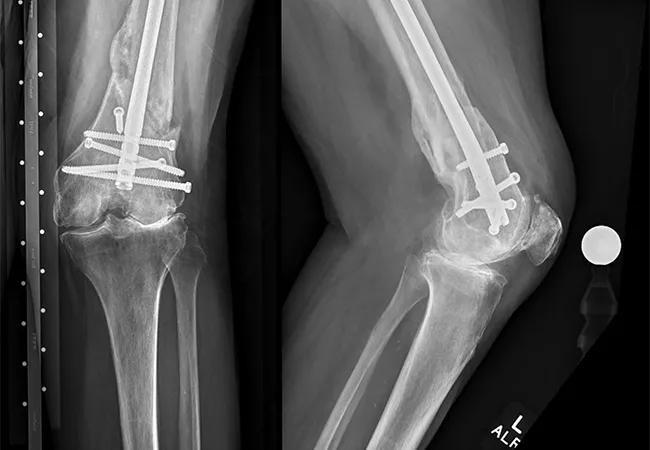

X-ray of healed fracture

X-rays show the retrograde intramedullary nail in place with interlocking screws. The fracture has completely healed, but a severe valgus deformity has developed, along with arthritic changes to the knee.